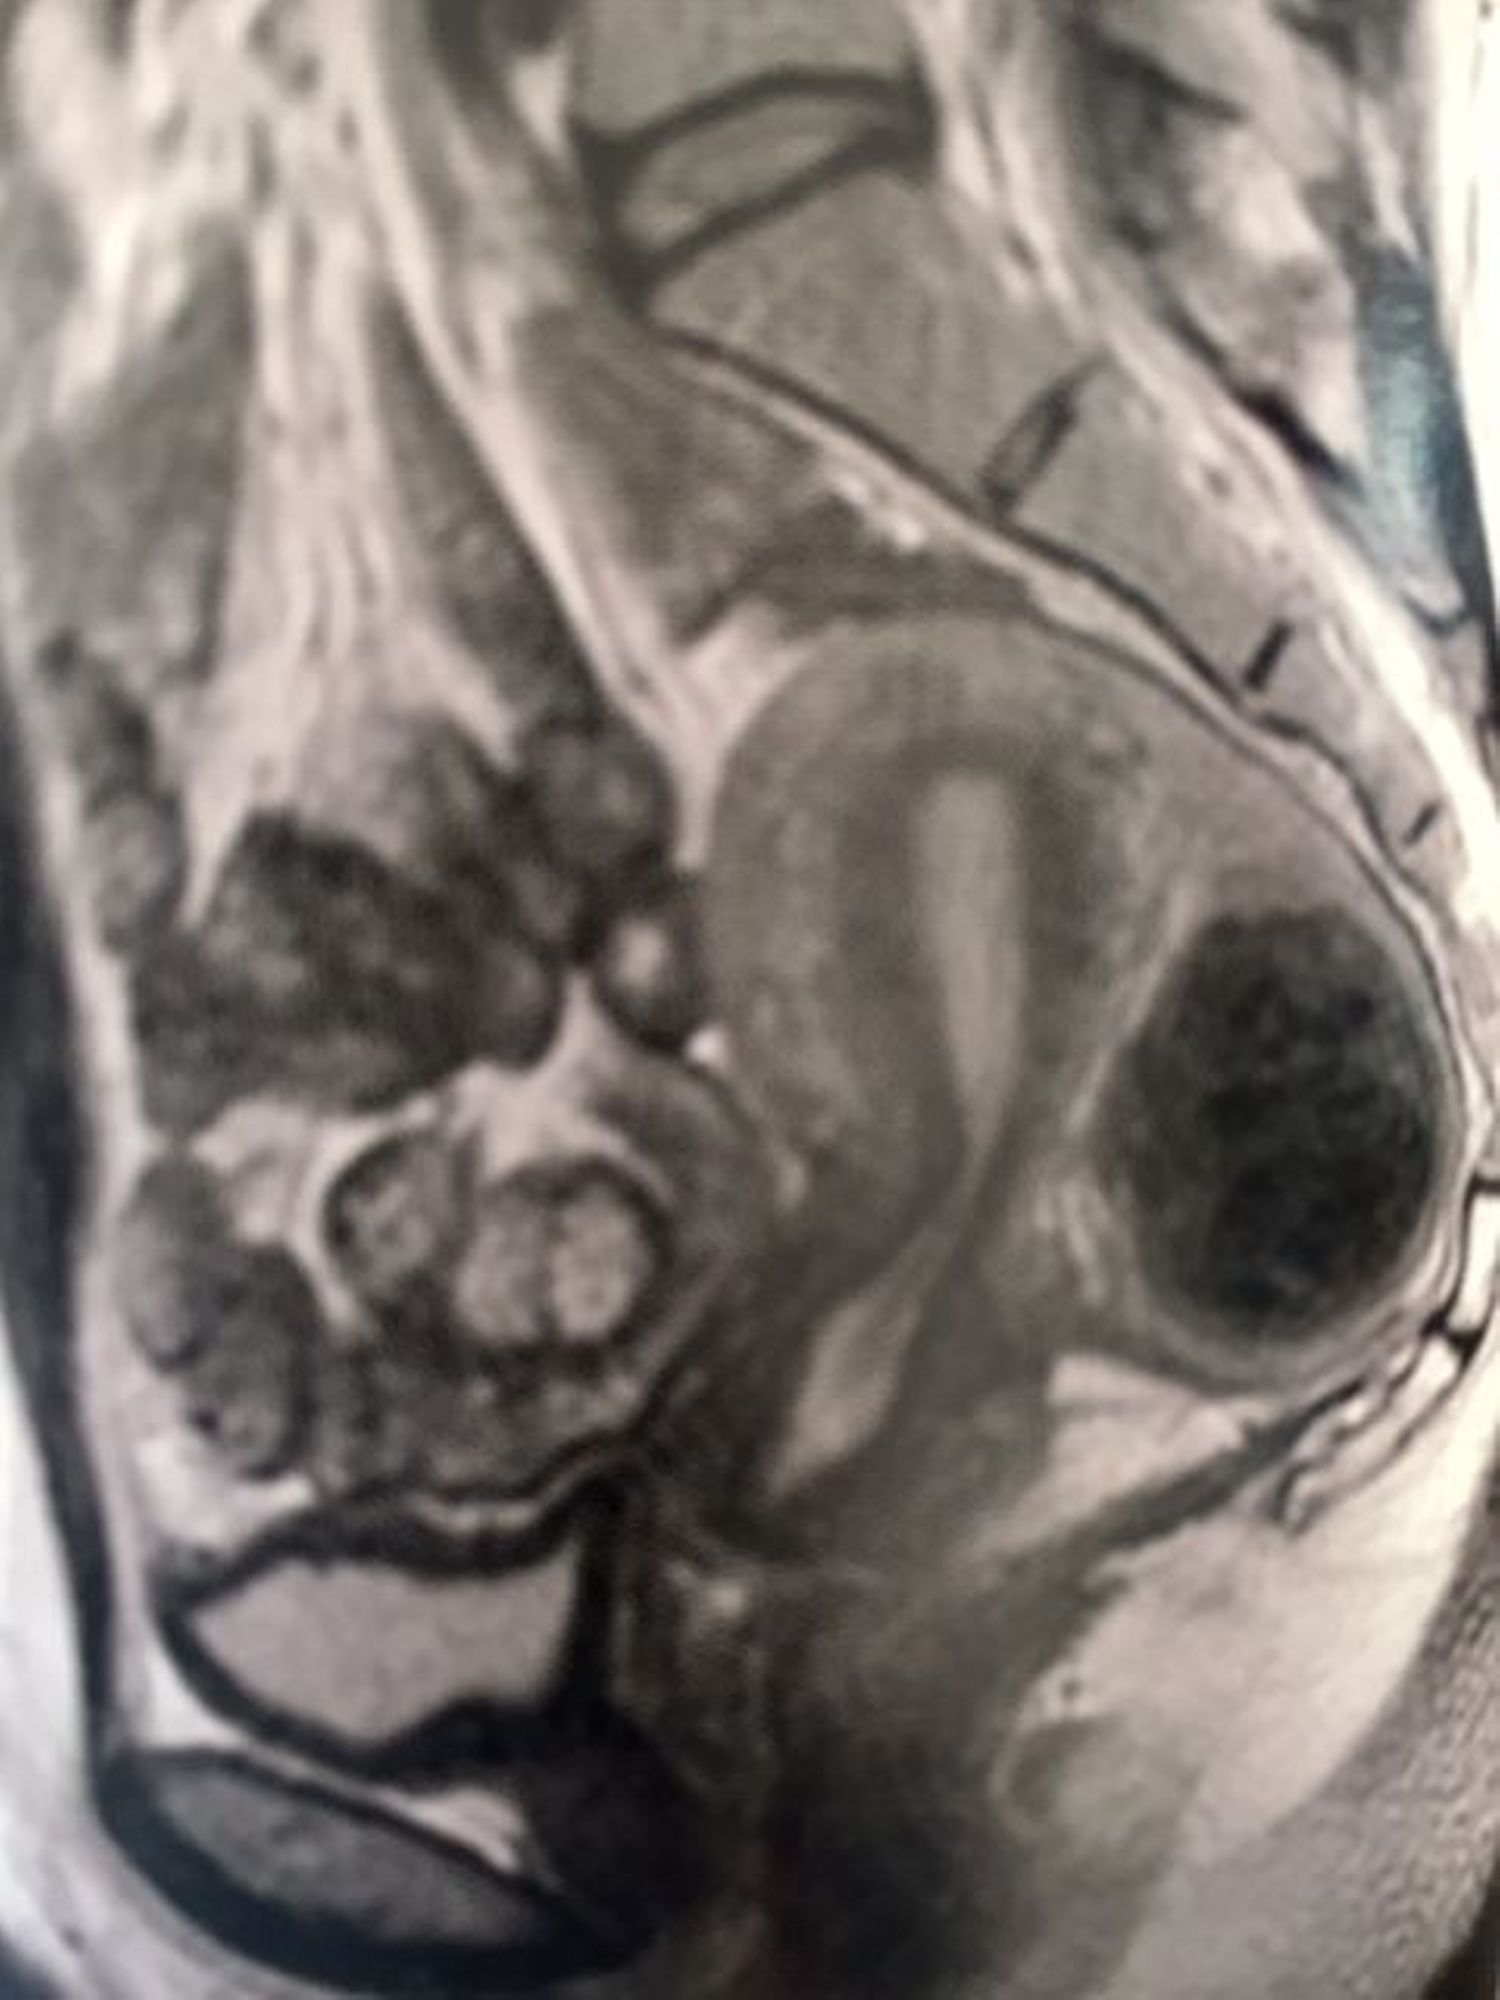

• La chirurgie ovarienne :

L'ovaire sera respecté AU MAXIMUM POUR PRESERVER  la réserve ovarienne.

Un kyste gênant pourra être retiré = kystectomie...

Le SOPK sera traitée en drilling (mini-perforations de la corticale ovarienne) par voie fertiloscopique ou cœlioscopie avec une réelle amélioration du fonctionnement ovarien et à la clef un taux de grossesse optimalisé.

• L'endométriose :

C’est une maladie à  multifacette nous imposera un traitement adapté sur le péritoine (cautérisation ou ablation de nodules), les ligaments utérosacrées  afin de réduire les douleurs et l'inflammation source d'infertilité.

Dans tous les cas, l'endoscopie permettra une classification de l'endométriose pour décider de l’orientation thérapeutique adaptée. L'ovaire endométriosique sera respecté dans la mesure du possible mais toujours libéré des adhérences.

• La chirurgie utérine :

On pourra retirer un polype ou un fibrome ou une zone d’adénomyose par voie naturelle (= hystéroscopique).